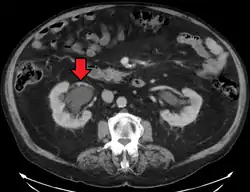

CT scan of bilateral hydronephrosis due to a bladder cancer

- Stone causing hydronephrosis[13]